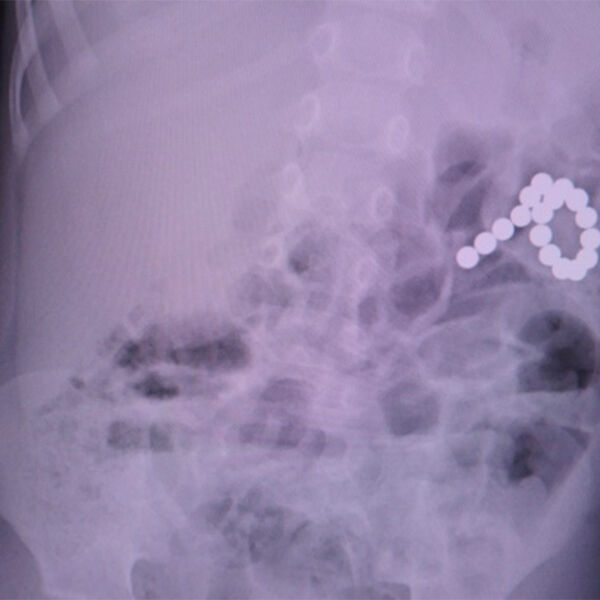

Хирурги ЯНАО прооперировали мальчика с 17 магнитами в желудке и кишечнике

На Ямале врачи извлекли из двухлетнего ребенка 17 магнитных шариков

Врачи Ямала прооперировали ребенка, который проглотил 17 магнитных шариков. Об этом сообщает Департамент здравоохранения ЯНАО.

Изначально медики подозревали у двухлетнего мальчика коронавирус, но во время обследований в Ноябрьской городской больнице у него нашли детали от магнитного конструктора. Часть элементов осталась в желудке, остальные прошли в кишечник и проделали отверстия в органах.

Врачи оперативно прооперировали ребенка. Во время манипуляции из пациента извлекли шарики и зашили отверстия. На данный момент мальчик чувствует себя хорошо.

По словам хирурга, проводившего операцию, подобные конструкторы опасны для маленьких детей. Даже два магнита могут существенно навредить ребенку.